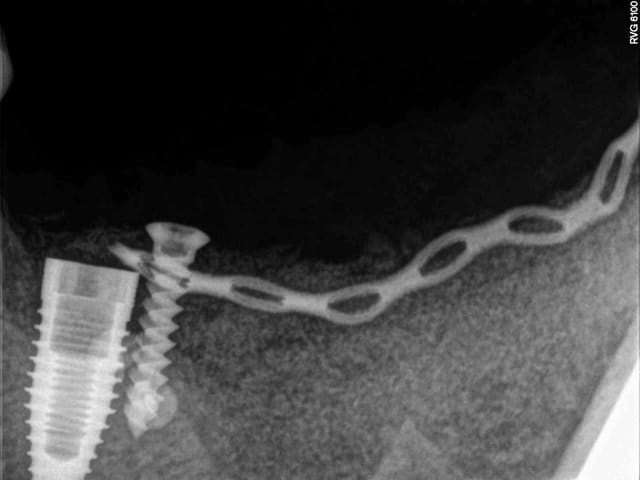

1- les vis et la chaine titane adaptée aux vis.

(pour expliquer: ce système permet de maintenir la chaîne en l'air par sa tête.)

4-5-6-7 sciage de la mesh titane et positionnement in situ d'un bout à l'autre de l'arcade.